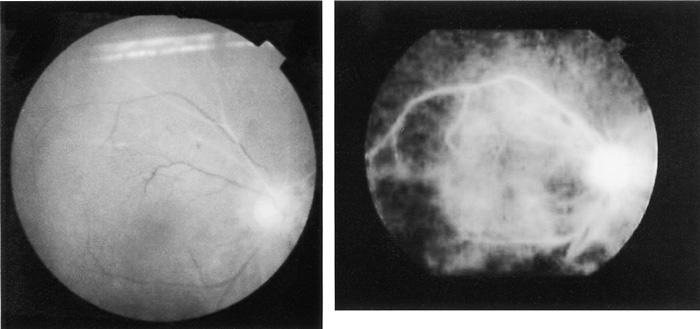

Fundus photograph (A) and fluorescein angiogram (B) of the right eye showing delayed dye infusion into the temporal and nasal superior retinal arteries and in the optic disc.